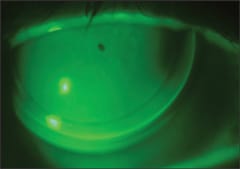

On the other end of the spectrum was a patient who presented with the most challenging post-RK corneas I've ever seen. Figure 2 shows the better right eye; the left eye had no less than 20 densely scarred incisions and developed hydrops that required penetrating keratoplasty shortly after his fitting visit.

For the right eye, we achieved success with a reverse geometry lens design that provided 20/25 acuity on this severely distorted cornea that had nearly 9.00D of irregular corneal astigmatism centrally. I wasn't satisfied with the fit — in fact, I had a hard time letting the patient leave with the lens. But there was tear exchange and the patient was comfortable with good visual acuity. He was satisfied with the lens.

Figure 2. This sub-optimal-looking fit provided good vision and comfort.